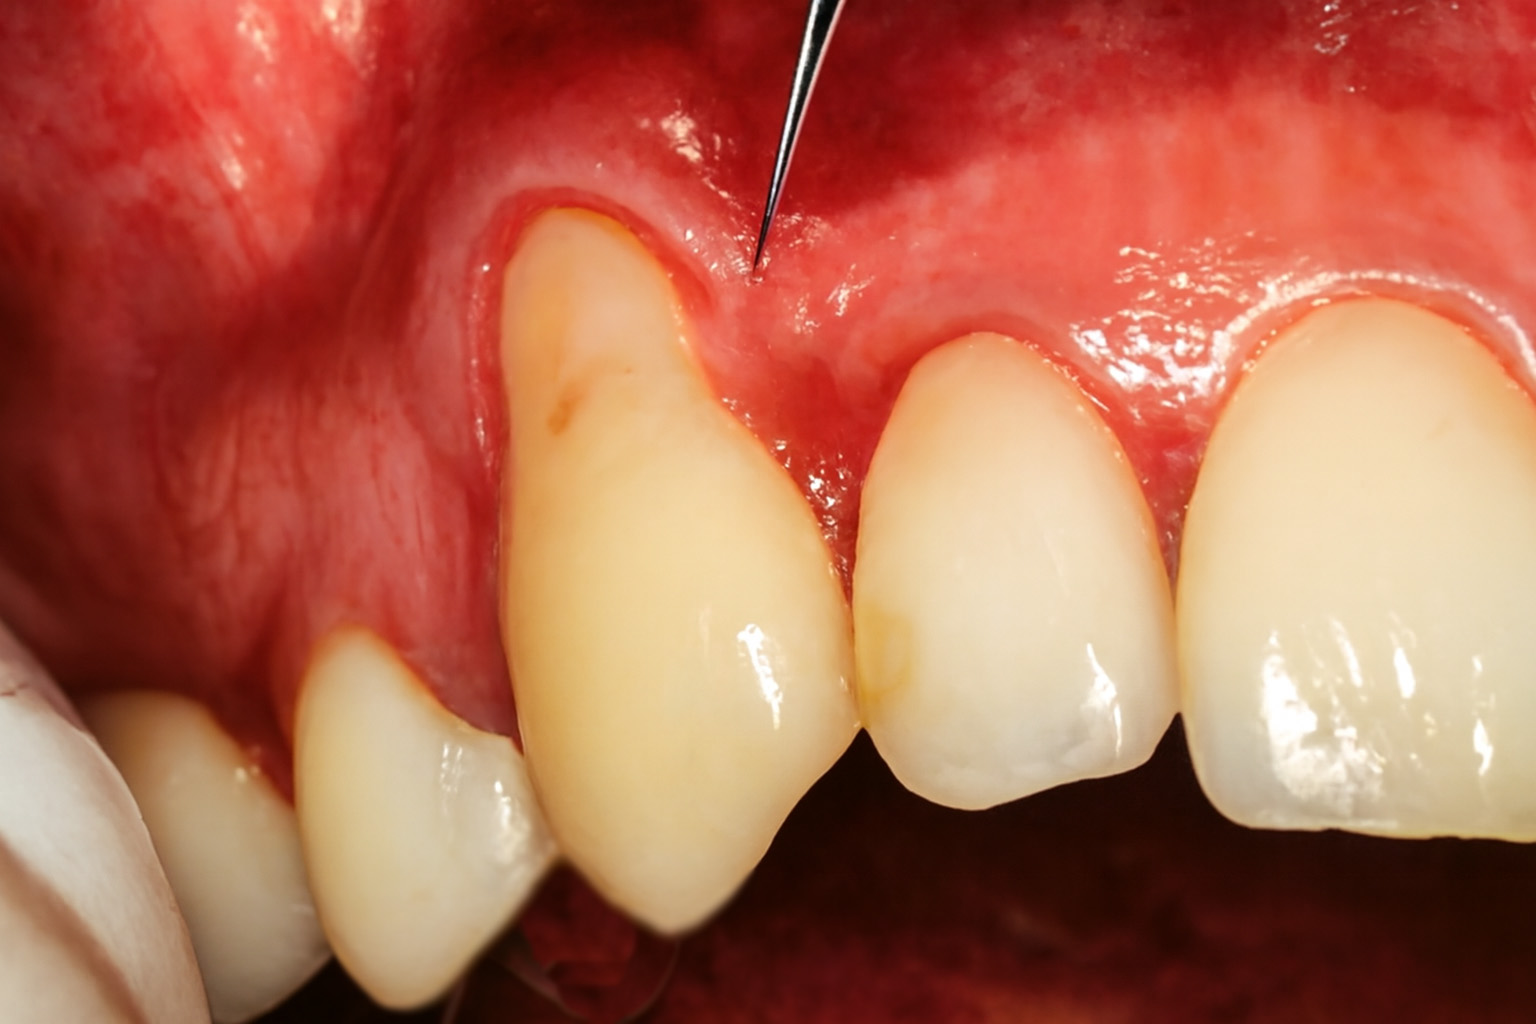

When your gums recede, the roots of the teeth may become visible. This can increase the risk of cavities in the root of the tooth.

Pinhole Surgical Technique (PST™) is an innovative and minimally invasive procedure for the treatment of gum recession. The technique, coined by Dr. John Chow, has revolutionized the gum repair procedure, offering patients a faster and more convenient alternative to traditional gum transplantation procedures.

Pinhole® Surgical Technique (PST™) is a specialized procedure for correcting gum recession without incisions, sutures, or transplants. This is achieved by making small holes in the gums near the affected areas.

Dr. Ghayoumi can gently loosen and insert the gums to cover the exposed tooth roots and restore a healthier gum line through these holes.